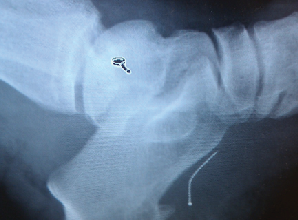

Always take standard radiographs after any puncture wound. X-rays can determine the presence of a retained foreign body or if any osseous structure has been breached. However, X-rays may be inadequate in the detection of small pieces of glass, wood or rubber. In those cases, advanced imaging studies may be necessary.

Computed tomography (CT) can provide superior imaging when it comes to detecting wood deep in tissues.10 Magnetic resonance imaging (MRI) may be helpful, especially in detecting osteomyelitis as MRI provides a precise anatomic location of the infection and assists the surgeon when planning surgical debridement.11 Ultrasound is a very helpful modality in detecting non-radiopaque foreign bodies and is cost-effective.

Radionuclide imaging is important and very helpful when one suspects osteomyelitis. Plain films do not detect osteomyelitis for 10 to 14 days after the establishment of bone infection. Technetium-99m-methylene diphosphonate (Tc99m MDP) bone scans are very sensitive and can detect bone infection within 24 hours of the onset of infection. However, Tc99m MDP has a low specificity. Therefore, tagged white blood cell scans (i.e. hexamethylpropyleneamine oxime scans) may be more specific for localizing infection.12